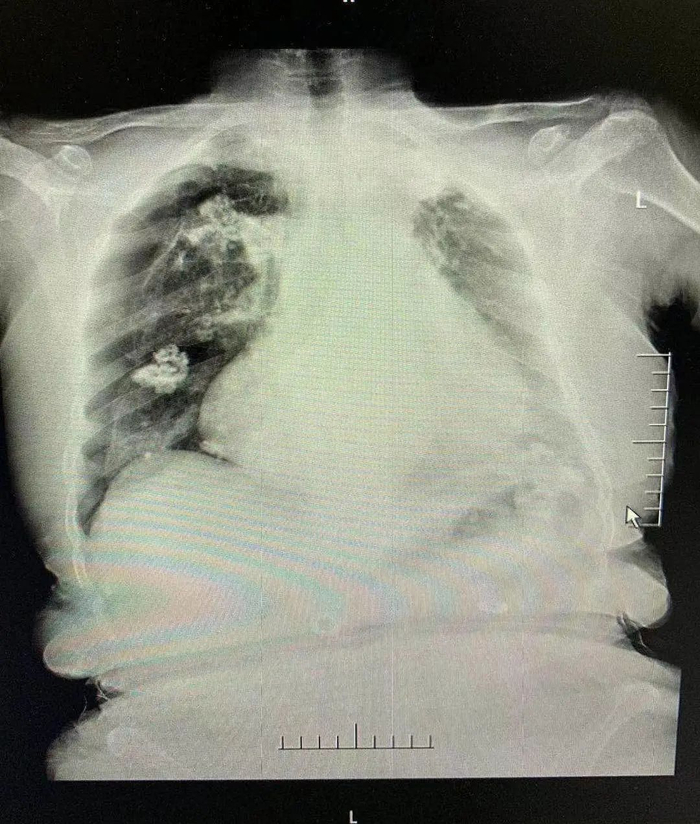

针灸扎穿肺,右肺压缩约50%

陶金医生告诉记者,得知这一情况后,院方立即安排急查床边胸片。最后胸片检查提示:右侧(针灸的一侧)气胸肺压缩50%!也就是说,浦阿姨的右肺被压缩得只剩下一半。一查原因,竟然是针灸不当错扎到肺部所致。

“这是一种‘肺漏气’的现象”,陶金解释,“这种现象的产生,是由于肺部内的气体泄漏到胸腔后,囤积在胸腔又压迫了肺。”而如果漏气得不到缓解,当肺部压缩到最小程度时,浦阿姨面临的将是“呼吸骤停”的威胁。